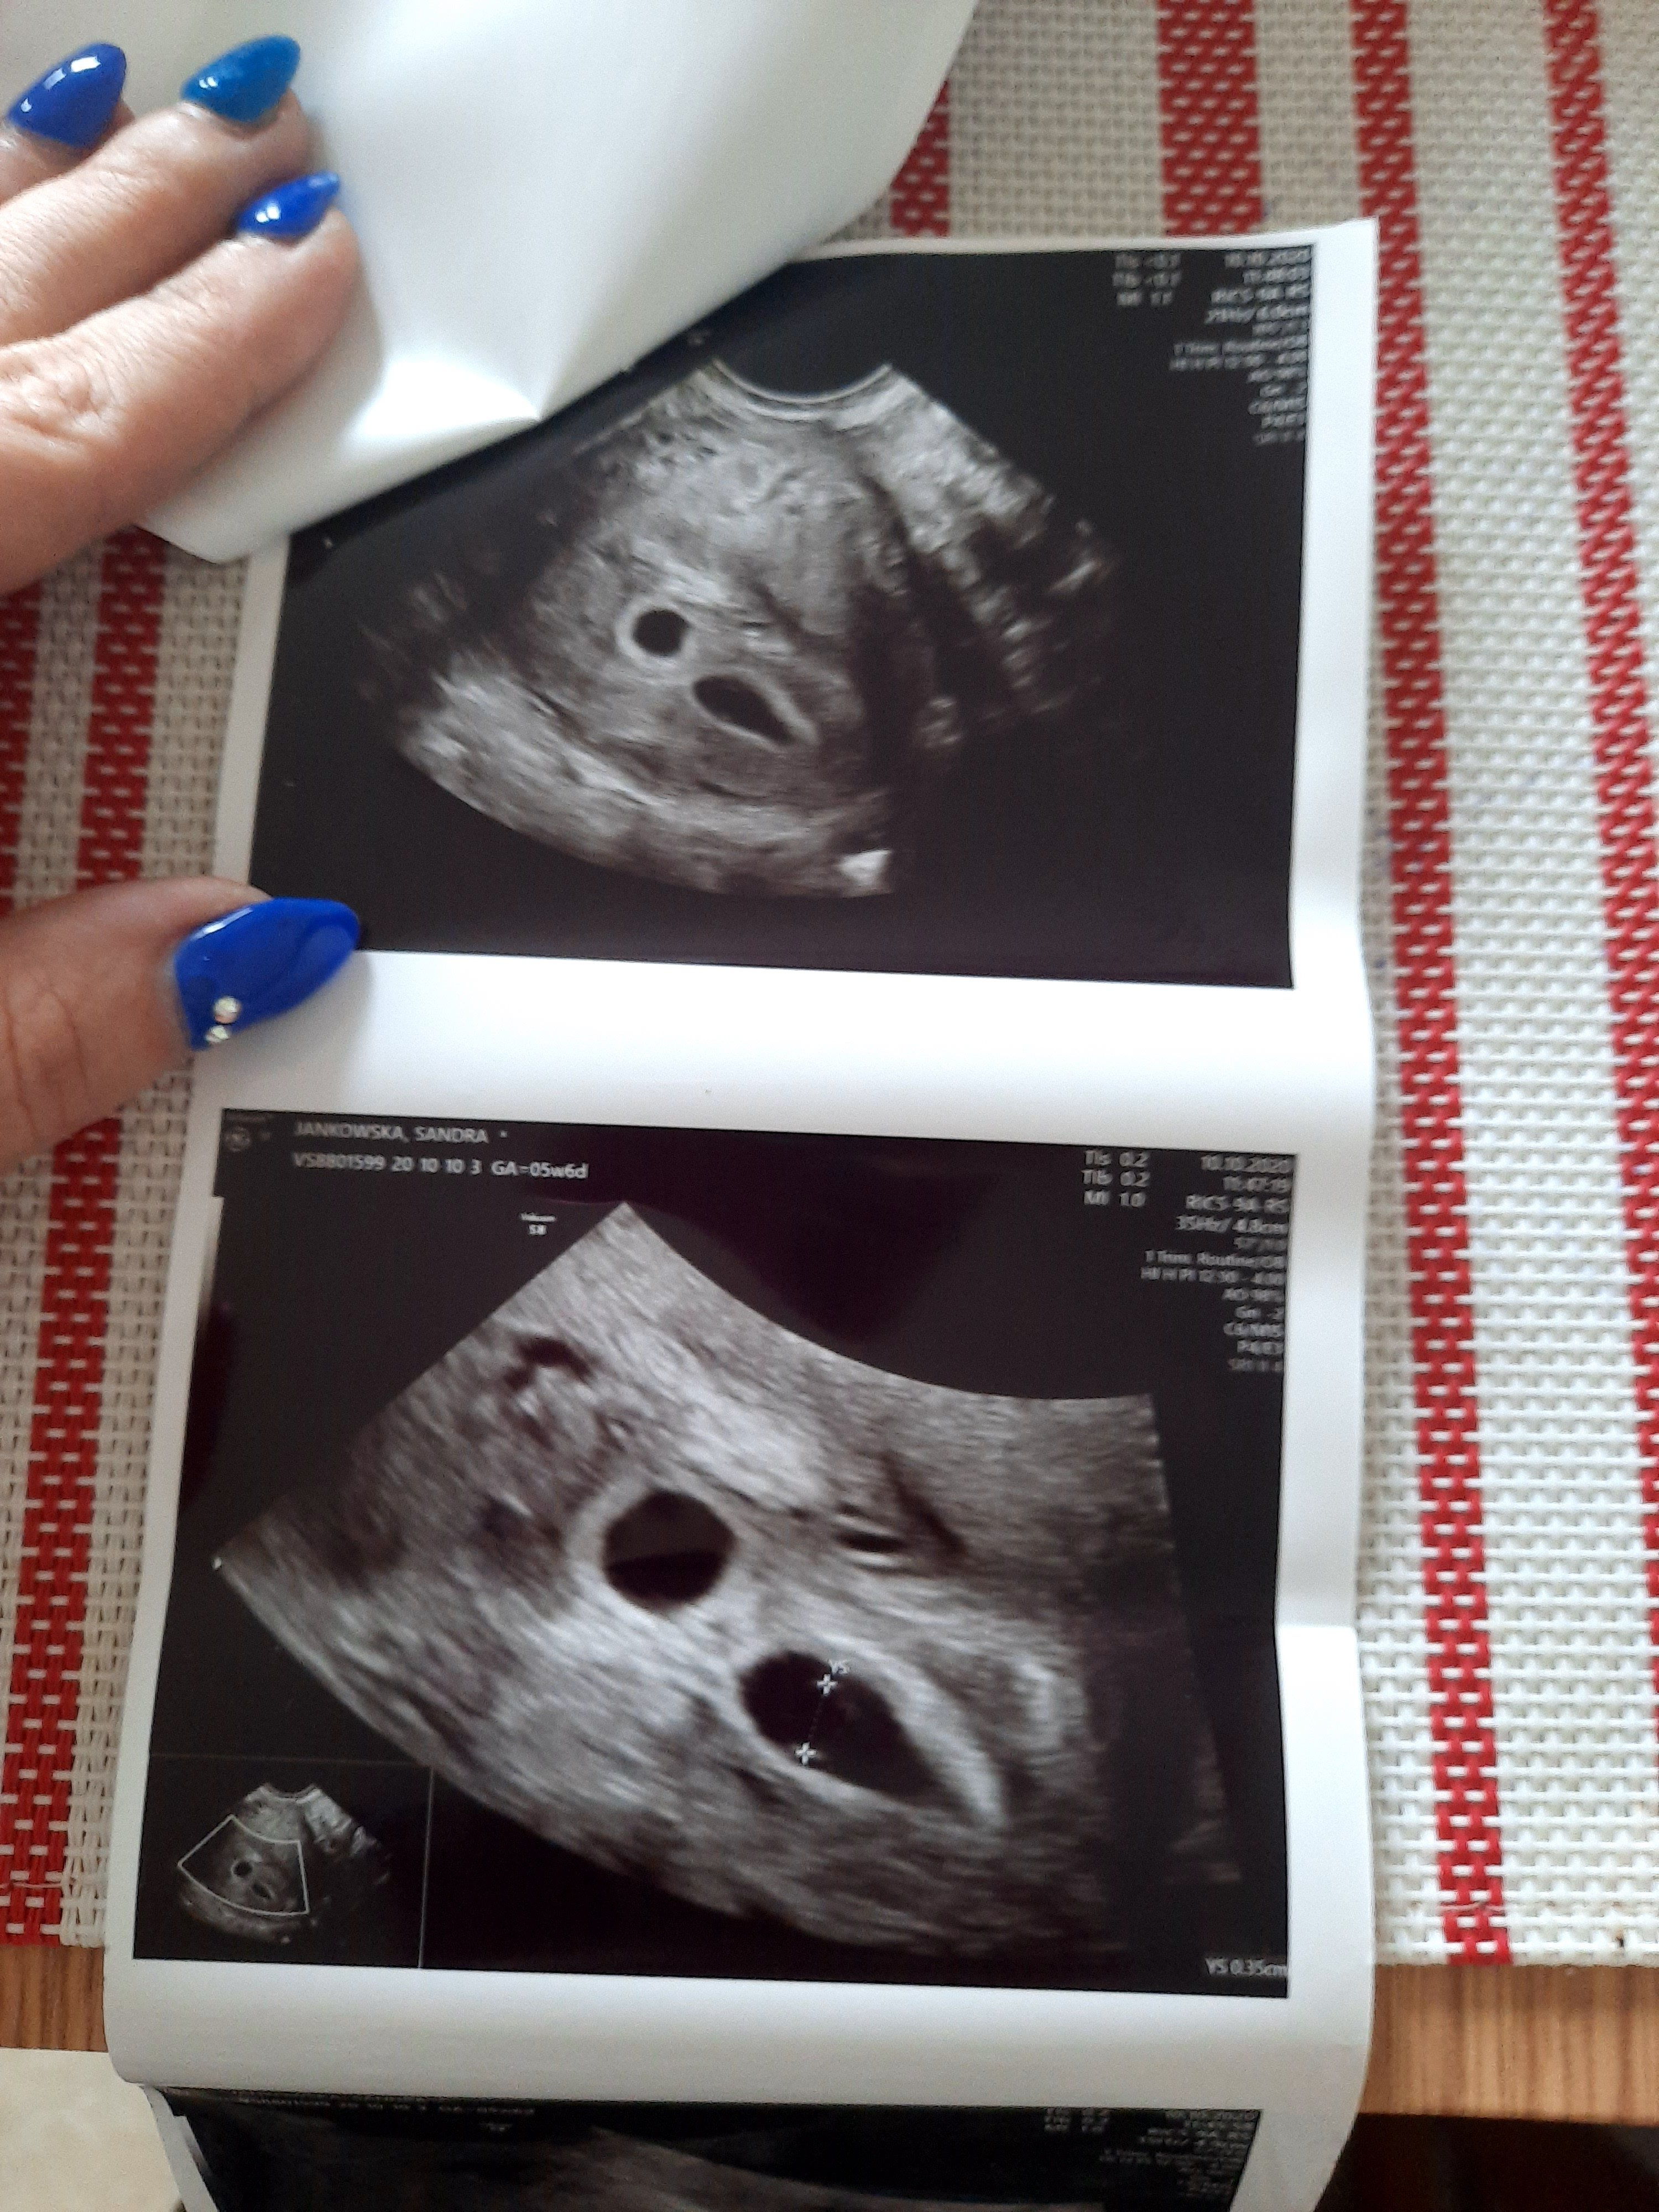

Już oficjalnie potwierdzona ciąża bliźniacza są dwa ciałka żółte. Wszystko rozwija się prawidłowo termin mam 6.06.21r ale może się zmienić 21.10 kolejna wizyta bo z automatu ciąże bliźniacze zalicza się do ciąż patologi.

Grunt że to nie puste jaja a obydwa nowe życia.

Bo tego się bałam. Dostałam luteine aby nie doszło do zatrzymania ciąży profilaktycznie.